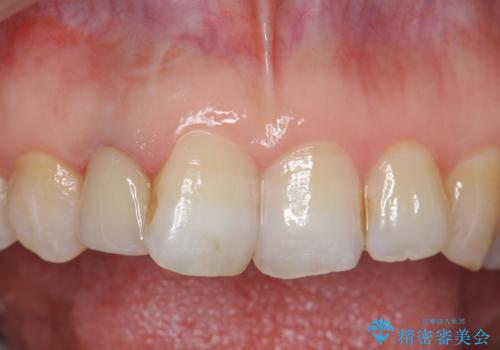

- 右上2番目の歯の変色が気になるといらっしゃった方の症例です。

再根管治療終了後、オールセラミッククラウンによる補綴を行いました。

今回用いたオールセラミッククラウンはジルコニアフレームという白い素材の上にセラミックを盛っているため、審美性が非常に高いのが特徴です。

また、ジルコニアは人工ダイヤモンドの材料にも使われているほど高い強度を持っており、そのためオールセラミッククラウンは審美性だけでなく、奥歯やブリッジの補綴も可能とするクラウンです。